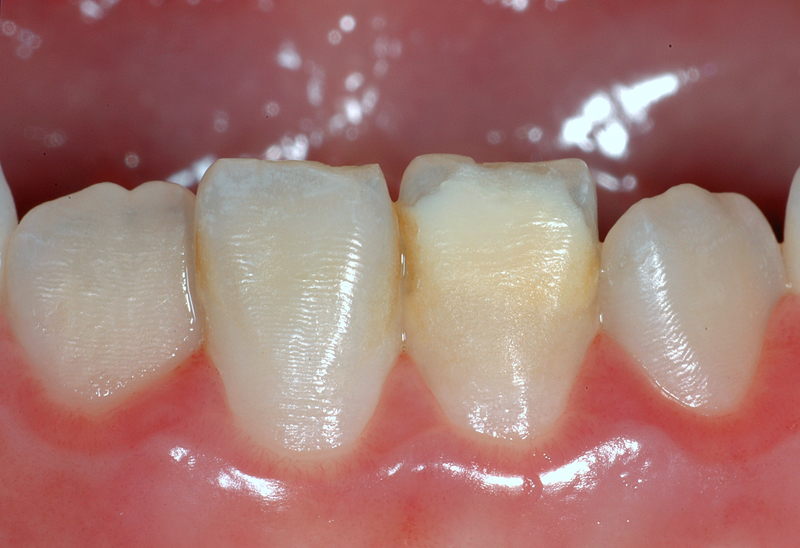

Hier ein Fall mit Zahnstein im Zahnzwischenraum der beiden unteren mittleren Schneidezähne und auf der Aussenfläche des rechten seitlichen Schneidezahnes.

Abhilfe: Professionelle Entfernung / Reinigung durch Prophylaxe-Assistentin.

- Zahnstein